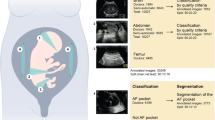

SWALLOWING movements are known to be made by the fœtus in utero, but the ability of the gut to absorb material from the amniotic fluid has received little attention. This latter aspect has been investigated in fœtal sheep over the age-range 80–145 days (full term).